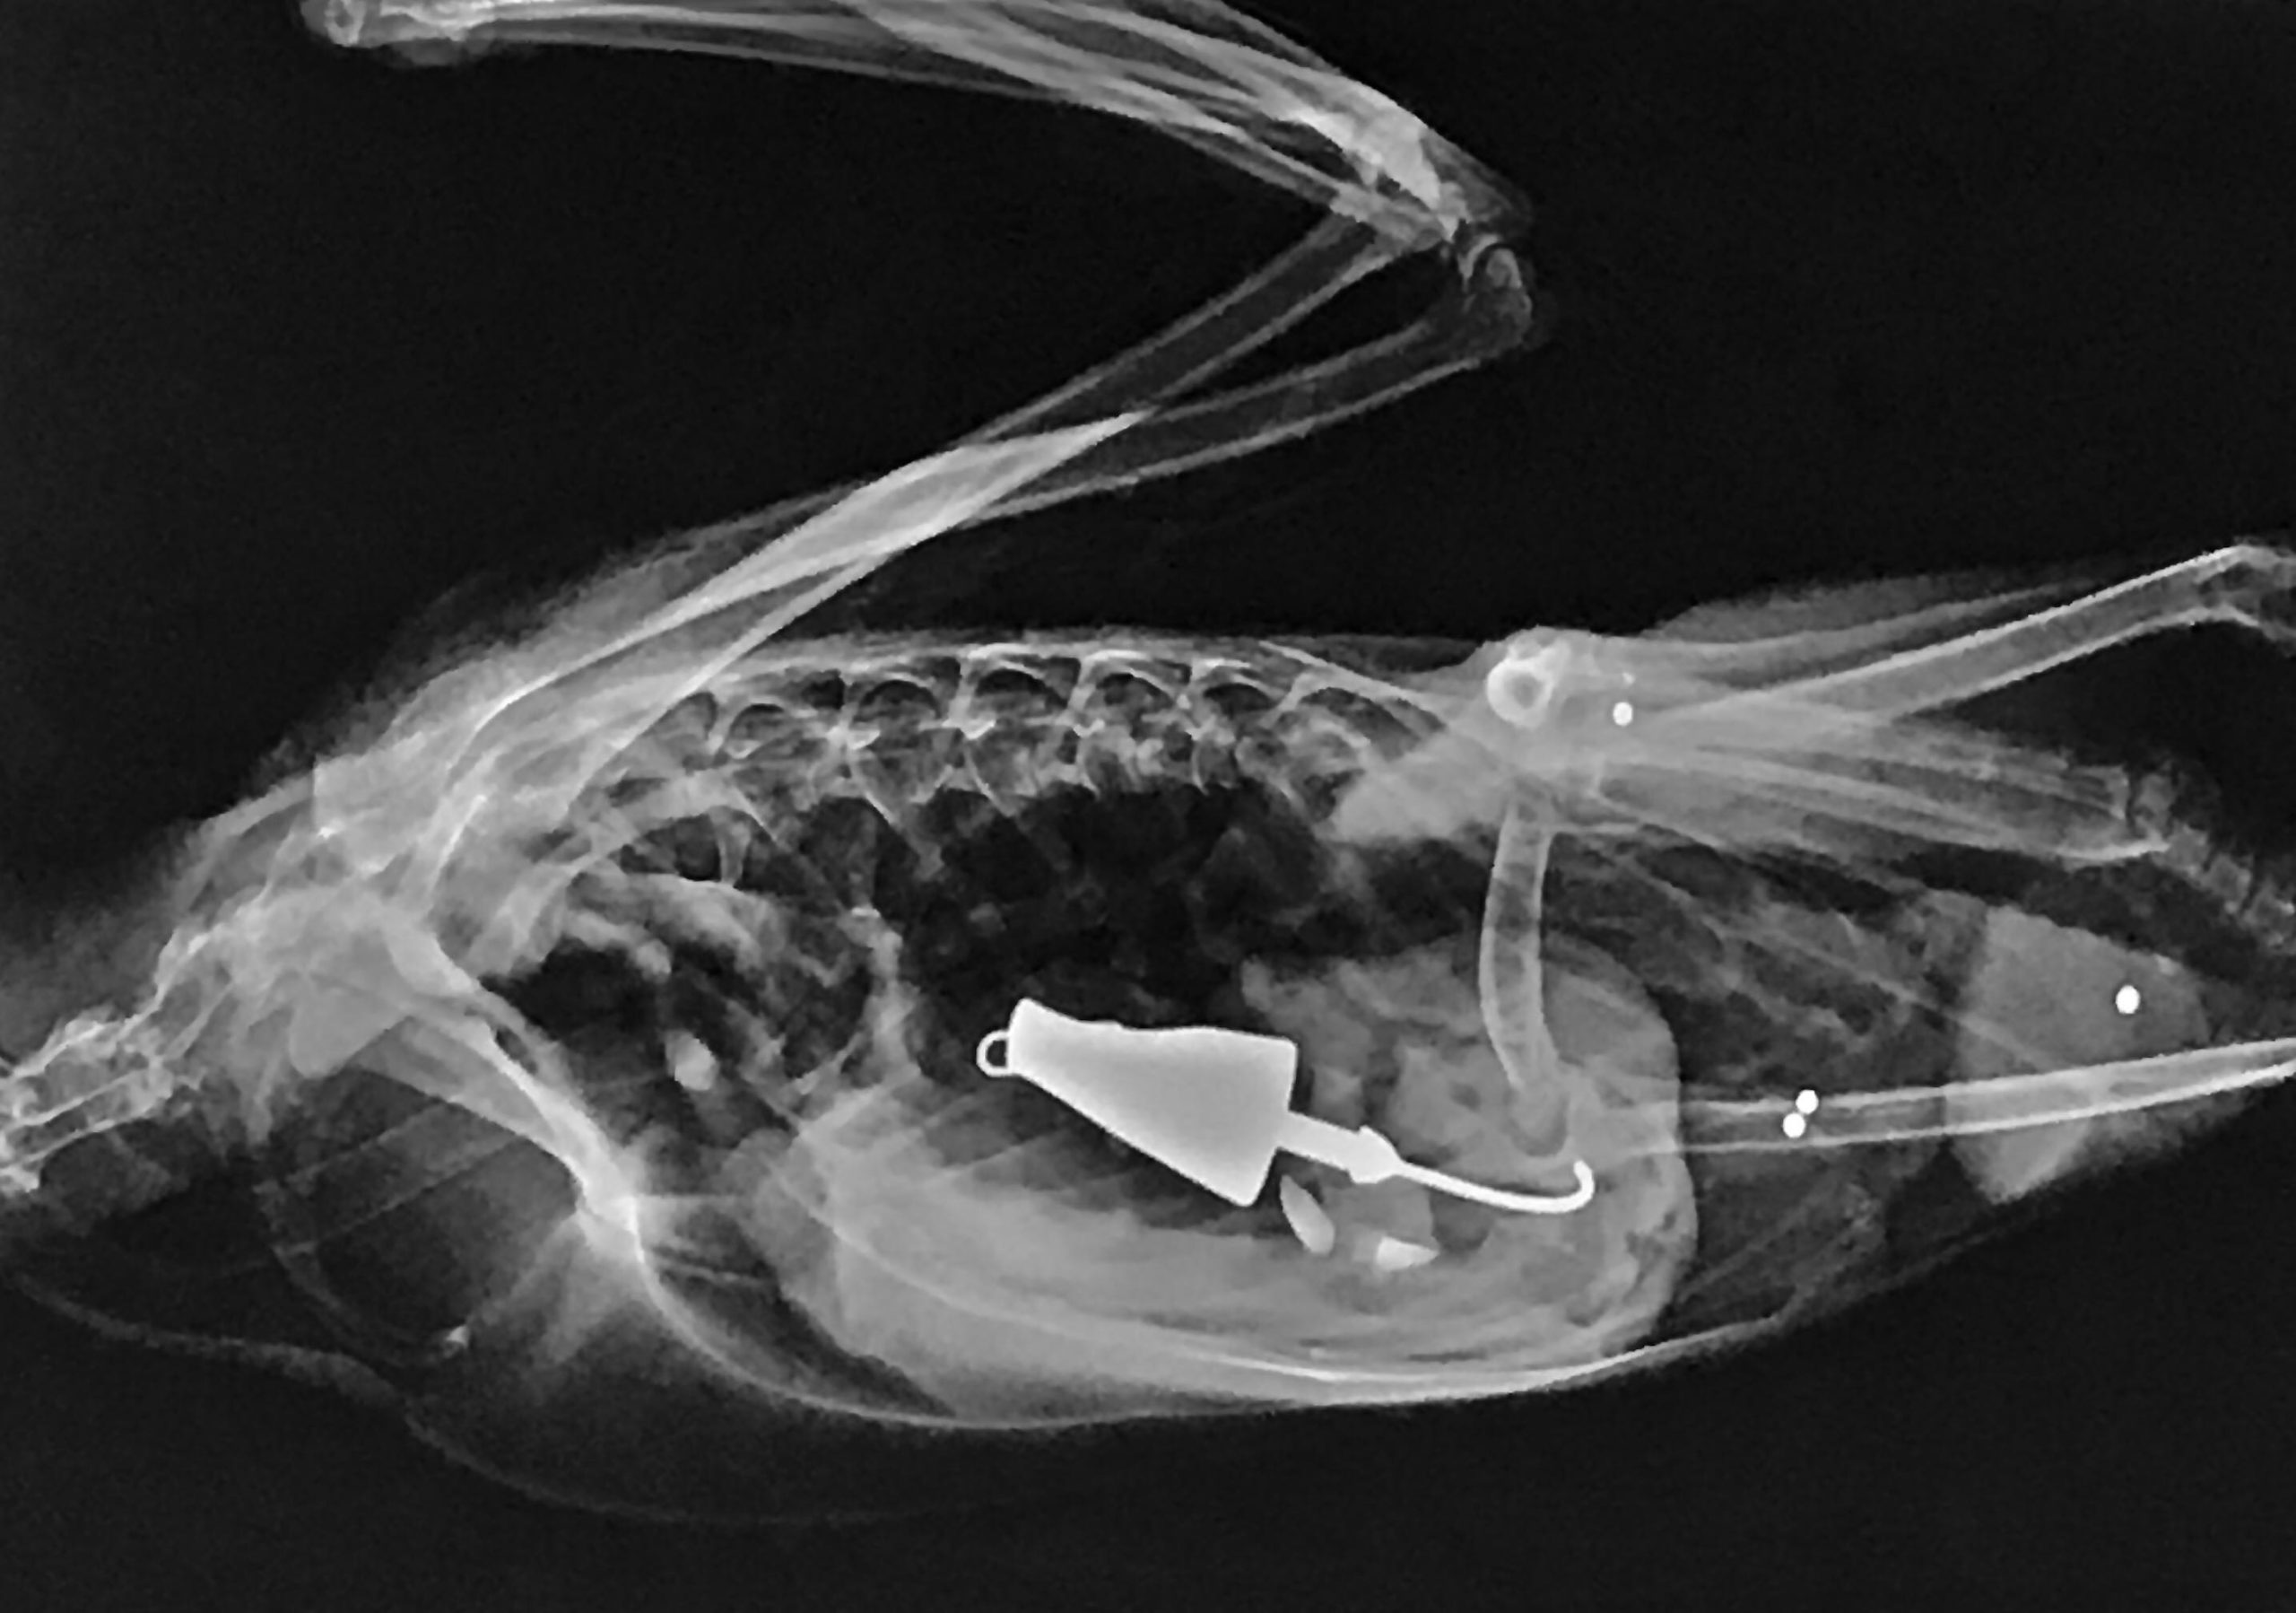

This snapping turtle originally presented to the clinic because a Good Samaritan had seen the fishing line and assumed there was a hook attached. On radiographs, we were surprised to find two hooks, one within the esophagus (and attached to the fishing line) and one within the stomach.

Wild animals are negatively impacted in many ways by littered fishing equipment. This Canada goose underwent surgery at the clinic to remove a lure that it had ingested.